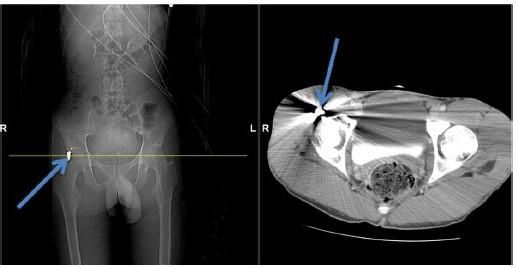

Динамічна стабілізація хребта передбачає застосування так званих гнучких фіксаційних систем – рухомих протезів міжхребцевих дисків, гнучких стержнів для скріплення імплантів та кісткових структур хребта, а також так званих амортизаторів – гнучких міжхребцевих імплантів, що регулюють діапазон рухів уражених хребців.

Суть використання динамічних систем стабілізації хребта – це відновлення природної анатомічної геометрії хребта зі збереженням його біомеханічних властивостей, без жорсткого блокування хребців, з максимальною фізіологічною рухливістю в хребетно-рухових сегментах.